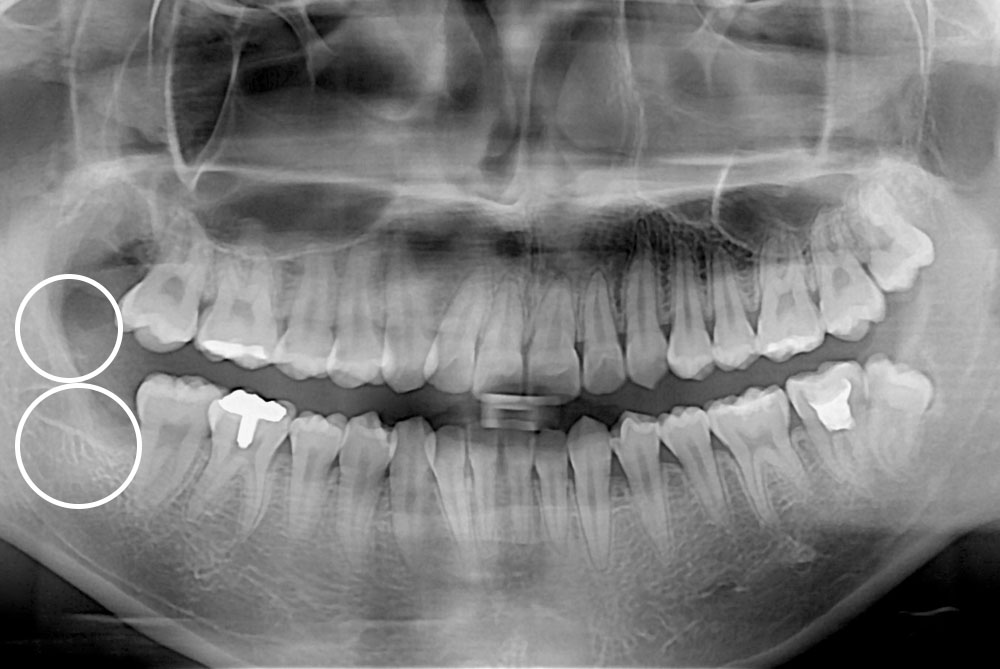

[사랑니] 매복 사랑니 발치

치료전 : 2018-03-06